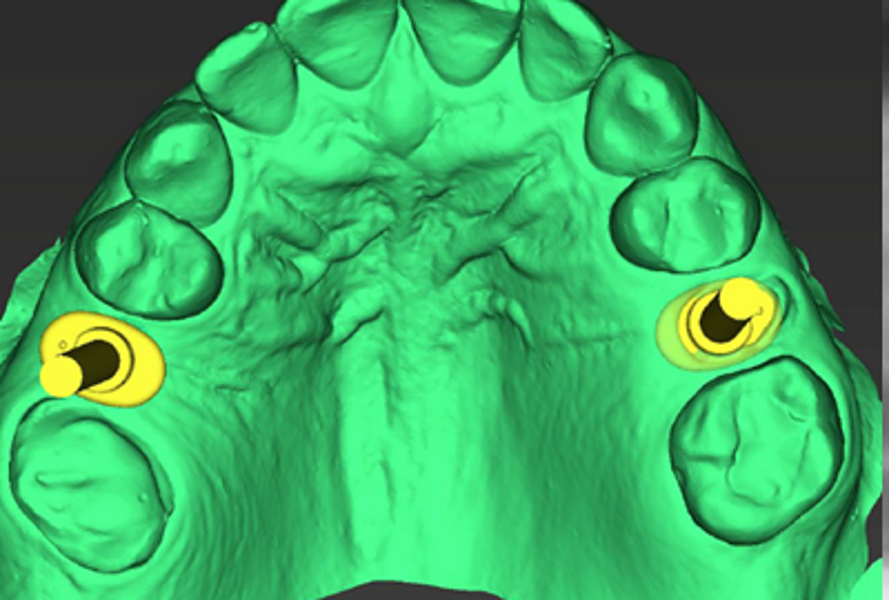

The patient’s maxillary and mandibular arches were scanned using the Straumann SIRIOS system. The scans, along with the DICOM files from the CBCT scan, were sent via Straumann AXS to Smile in a Box (Straumann) for treatment planning, surgical guide design and 3D printing of the model and surgical guides (Figs. 4, 5a–f & Figs. 6a–d).

After evaluation and validation of the plan, it was decided for site #15—where a residual root was present and the bone density was generally soft—that a Straumann BLX (Roxolid, SLActive, regular base) 4.5 × 8.0 mm implant would be placed, along with an M shape Straumann Anatomic Healing Abutment XC (regular base/wide base; gingival height: 1.5 mm). For site #25, extraction of the remaining root was planned and would be followed by the placement of a Straumann BLC (Roxolid, SLActive, regular base) 3.75 × 8.00 mm implant. This narrower site had a visible lamina dura, favourable for achieving primary stability. An M shape Straumann Anatomic Healing Abutment XC (regular base/wide base; gingival height: 1.5 mm) was also selected for this site to support proper soft-tissue emergence during the 60- to 90-day healing period. Owing to the expected post-extraction gaps between the implants and buccal bone walls, cerabone plus (botiss biomaterials) was planned to be used for grafting.